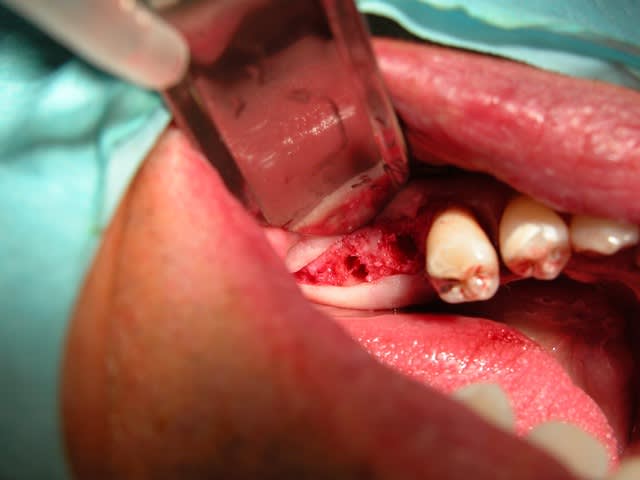

Et moi j'avais besoin d'os pour combler au maxillaire!

C'est facile à recuperer d'un coup de maillet ciseau ,et c'est de l'os autogène